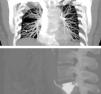

A fifty-year-old woman, never smoker, with an L5 vertebroplasty performed four years previously was referred to our unit because of a radiographic finding. The patient had had dyspnea on heavy exertion for four years, episodes of chest tightness and palpitations. Physical examination was normal. CT images revealed a calcific density foreign body in the left pulmonary artery and similar smaller masses in the right chest. A leakage of vertebral cement could be observed at the level of the L5 vertebra, communicating with the left common iliac vein.

The patient was diagnosed with pulmonary embolism (PE) of polymethyl methacrylate (PMMA), a material used as cement in vertebroplasty. Cement leakage to peripheral tissues during the procedure is the most common complication. PE occurs in 3.4–23% of vertebroplasties performed for osteoporotic fractures,1 and is asymptomatic in most cases. Immediate postoperative management of PE is based on the presence of symptoms and the location of the embolization. Observation is recommended in asymptomatic cases, 3–6 months of anticoagulation therapy is recommended in symptomatic cases and in those with central emboli, and surgery is required in severe cases.